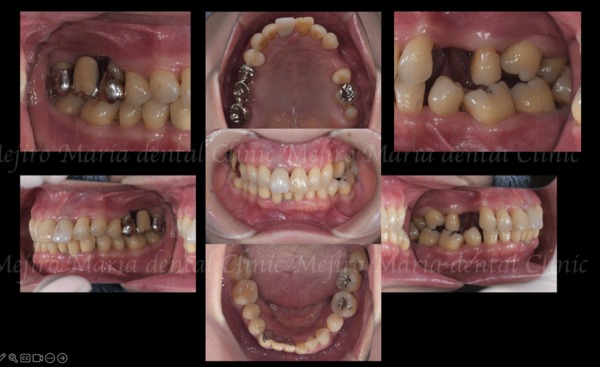

治療前の状態・主訴

患者様は50代女性で、右上の歯肉の腫れと歯の動揺を主訴に来院されました。

正面からの見た目だけでは一見問題が無いように見えるものの、以前左側の複数の歯を抜歯したまま放置していたため、歯が前方に傾斜し、噛み合わせが大きく崩れていました。

長期間、噛み合わせの悪い左側を避けて右側だけで噛んでいたことにより、右上の歯周病が過度な力によって進行したものと考えられます。

この時点での問題点:

・右上の歯は保存できる状態ではない

・右上の咬合支持喪失により両側臼歯の機能が破綻している

・その結果、前歯へ過剰な負担が移行し、将来的に歯周病で多くの歯が喪失されることが予想される